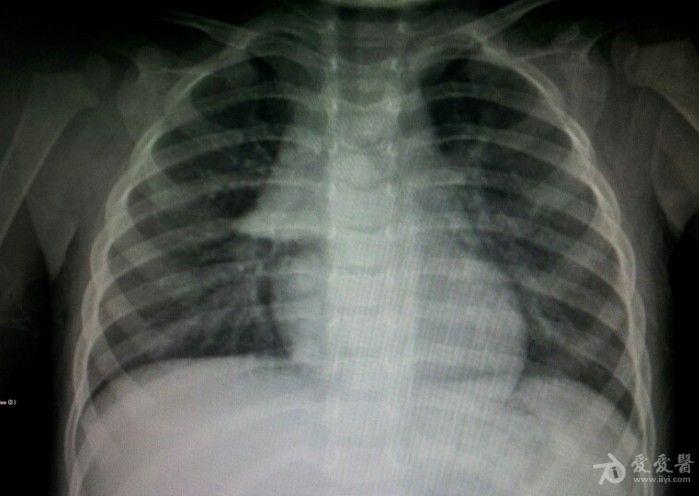

小孩正常胸腺——【船帆征】

还是正常胸腺影?

儿童胸腺的正常

儿科必备技能3大征象12张图片教你认识胸腺影像